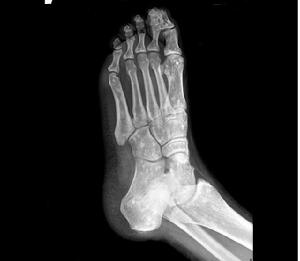

X线表现 可见圆形或卵子圆形的緻密斑点,几乎波及全身,特别是在长骨的骨骺部位及干骺端,但骨干很少有斑点。斑点的大小不一,直径大约由2mm~10mm数目不等。在脊柱、肋骨及锁骨均少见,在颅骨更稀有。骨骼的轮廓改变,骨骺发育亦无影响,关节间隙正常。在成人,斑点一般不再有明显变化,而在儿童则斑点可以增加,消失及融合。 医学百科网 | YxBaike.Com

本病可合并先天性畸形,如多指(趾)、并指、腭裂等。本组有1例为双足六趾畸形。 医学百科网 | YxBaike.Com

(3)病灶呈弥漫性多发的密度增大的圆形、椭圆形、圆圈状、结节状阴影,其形态走行,部分与骨的长轴一致。

(4)病灶多累及长骨的两端,密集于干骺端及骨骺,以及骨盆、手、足及不规则骨。越靠近关节病灶越密集,且密度越浓。病灶可相互融合成片而遮盖正常骨组织。 医学百科网 | YxBaike.Com

(5)密度增浓的斑点状病灶的边缘不甚清晰锐利,越靠近中心部位密度越浓,边缘部位密度略淡。

(6)病灶侵及骨的松质骨。骨膜及关节软骨不受侵犯,故关节间隙光整清晰。 医学百科网 | YxBaike.Com

脆弱性骨硬化本病好发于长短管状骨的骨端骨松质内以及肩胛骨、骨盆、腕骨、足骨等扁骨和不规则骨内,很少发生于骨干,在脊柱、肋骨、锁骨、颅骨内极罕见。 医学百科网 | YxBaike.Com

1、X 线检查是发现和诊断本病的主要依据。X 线上病灶呈弥漫多发的圆形、类圆形或融合成条状及团块状致密影,位于骨松质内,走行与骨长轴一致,双侧基本对称,大小在数毫米至2 cm 之间;越靠近关节病灶越密集密度也越高;绝大多数病灶中心密度高边缘密度低,也有少数病灶中心密度偏低,但其边缘均较清楚;病灶不侵犯骨膜及关节软骨,关节间隙清晰。